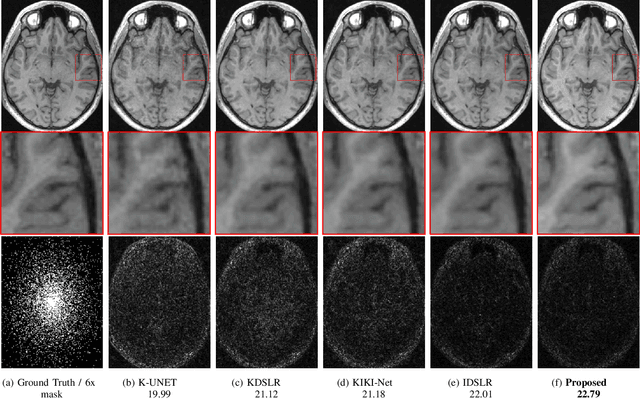

Abstract:The main focus of this work is a novel framework for the joint reconstruction and segmentation of parallel MRI (PMRI) brain data. We introduce an image domain deep network for calibrationless recovery of undersampled PMRI data. The proposed approach is the deep-learning (DL) based generalization of local low-rank based approaches for uncalibrated PMRI recovery including CLEAR [6]. Since the image domain approach exploits additional annihilation relations compared to k-space based approaches, we expect it to offer improved performance. To minimize segmentation errors resulting from undersampling artifacts, we combined the proposed scheme with a segmentation network and trained it in an end-to-end fashion. In addition to reducing segmentation errors, this approach also offers improved reconstruction performance by reducing overfitting; the reconstructed images exhibit reduced blurring and sharper edges than independently trained reconstruction network.

Abstract:We introduce a fast model based deep learning approach for calibrationless parallel MRI reconstruction. The proposed scheme is a non-linear generalization of structured low rank (SLR) methods that self learn linear annihilation filters from the same subject. It pre-learns non-linear annihilation relations in the Fourier domain from exemplar data. The pre-learning strategy significantly reduces the computational complexity, making the proposed scheme three orders of magnitude faster than SLR schemes. The proposed framework also allows the use of a complementary spatial domain prior; the hybrid regularization scheme offers improved performance over calibrated image domain MoDL approach. The calibrationless strategy minimizes potential mismatches between calibration data and the main scan, while eliminating the need for a fully sampled calibration region.

Abstract:Structured low-rank (SLR) algorithms are emerging as powerful image reconstruction approaches because they can capitalize on several signal properties, which conventional image-based approaches have difficulty in exploiting. The main challenge with this scheme that self learns an annihilation convolutional filterbank from the undersampled data is its high computational complexity. We introduce a deep-learning approach to quite significantly reduce the computational complexity of SLR schemes. Specifically, we pre-learn a CNN-based annihilation filterbank from exemplar data, which is used as a prior in a model-based reconstruction scheme. The CNN parameters are learned in an end-to-end fashion by un-rolling the iterative algorithm. The main difference of the proposed scheme with current model-based deep learning strategies is the learning of non-linear annihilation relations in Fourier space using a modelbased framework. The experimental comparisons show that the proposed scheme can offer similar performance as SLR schemes in the calibrationless parallel MRI setting, while reducing the run-time by around three orders of magnitude. We also combine the proposed scheme with image domain priors, which are complementary, thus further improving the performance over SLR schemes.